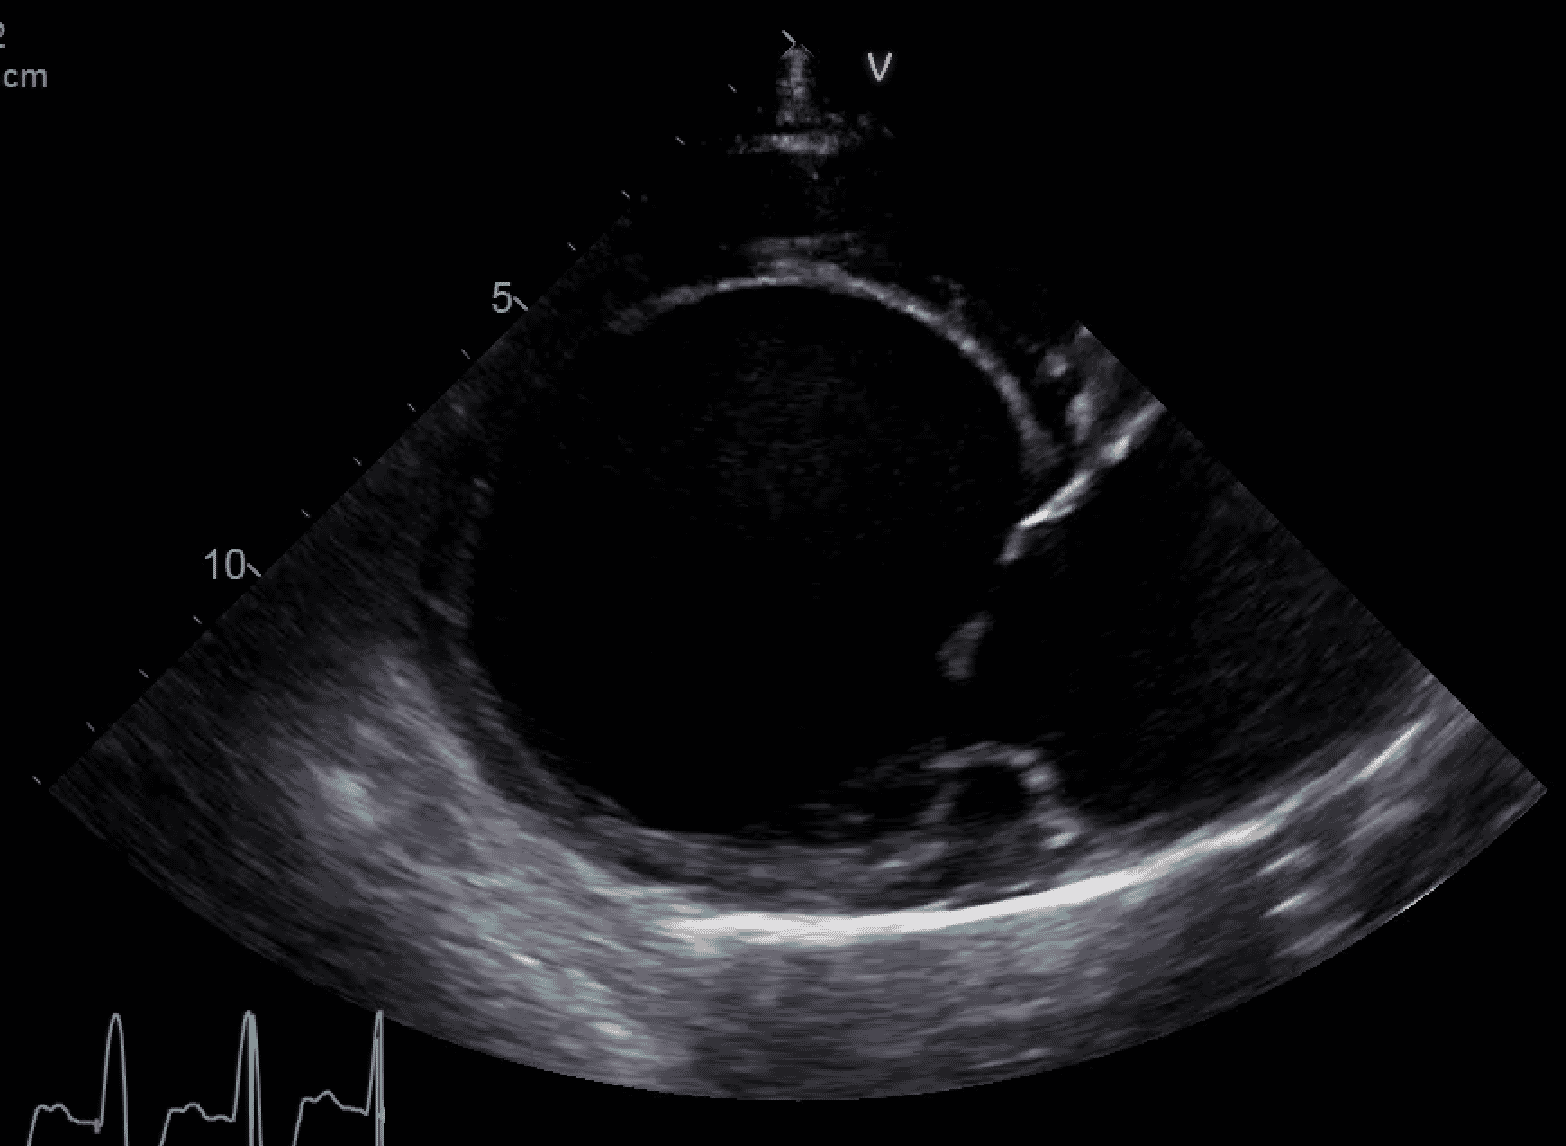

Here, we will be focusing on acute left-sided heart failure, caused by mitral valve disease (MVD) or dilated cardiomyopathy (DCM) ( Figures 1 and 2). In dogs, these make up probably 95 percent of the cases of heart failure identified in primary care practice, with the remaining being caused by arrhythmogenic right ventricular cardiomyopathy (especially in Boxers and Bulldogs), arrhythmia-induced heart failure (relatively common in working breeds) or congenital heart diseases such as patent ductus arteriosus (almost exclusively puppies of predisposed breeds).